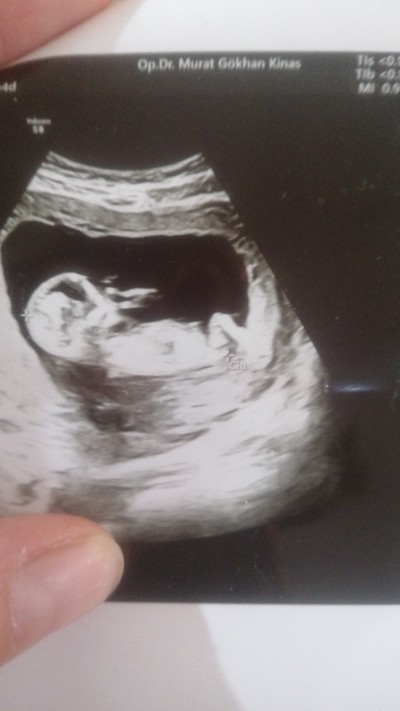

image

Ben kız diyorum masum oturusu var

Öyle benim postumda oğlumun duruşuna bak aynı mi